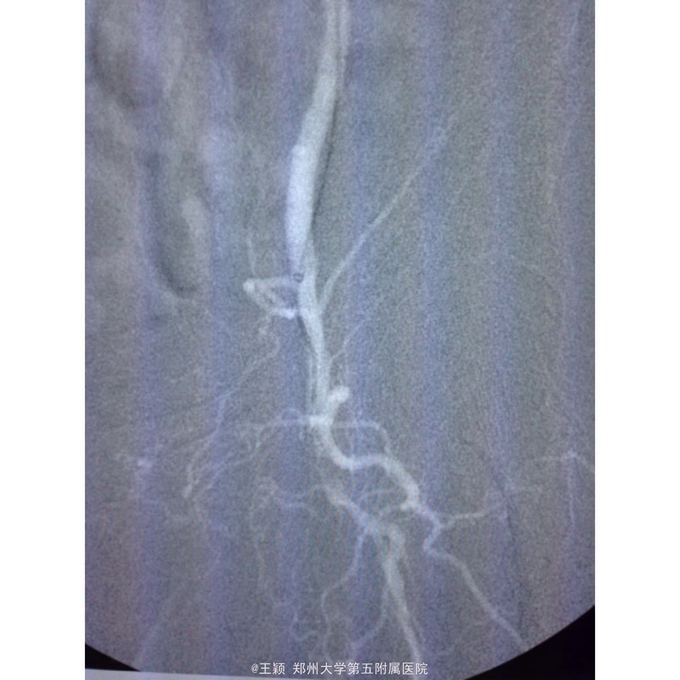

诊断为:下肢动脉硬化闭塞症D级并左足坏死 处理:85岁高龄患者,拟局麻翻山,先行处理左侧,术中患者不能配合,且造影发现左侧股总动脉远端近分叉处存在重度狭窄,钙化明显,即使顺利开通闭塞段,股总动脉的处理非常棘手,单纯球扩效果不佳,放置支架势必遮挡股深动脉,一旦出现问题,再次处理非常麻烦,综合考虑后改为全麻,局部切开后,剥脱股总及股浅动脉近段斑块,股浅动脉远端未进一步处理,术后造影,股总动脉远端狭窄解除,股深动脉显影较前改善,术后下肢皮温皮色均好转!